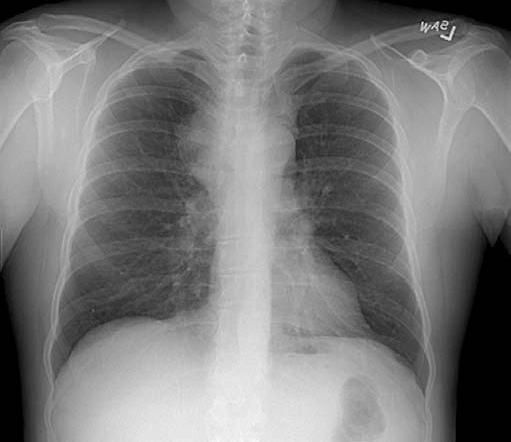

The patient's chest radiograph (Figure 1) and CT scan of the chest after administration of intravenous contrast material (Figure 2) are shown below.

Figure 1 Figure 2

The chest radiograph revealed fullness in the superior mediastinum with the trachea remaining midline. The margins of the aorta remained visible, suggesting that the mass was not in the posterior mediastinum, but was in either the anterior or middle mediastinum.

The most common finding on chest radiographs is mediastinal widening, followed by pleural effusion and a right paratracheal mass. In one analysis of 86 patients with SVC syndrome, 16% had normal chest radiographic findings.2